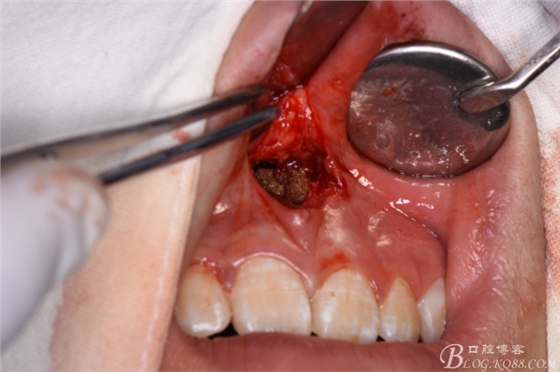

圖8.先拔除11、21之間多生牙,做唇側(cè)弧形切口

圖9.翻瓣、暴露唇側(cè)骨面,高速渦輪機去骨。

圖10.暴露出11、21之間的倒置多生牙牙冠

圖11.暴露出整個多生牙牙冠